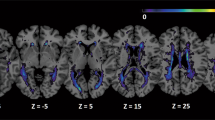

Table 1 summarizes the demographics and clinical features of RRMS (N = 68), NMOSD (N = 50), and 26 HC. The NMOSD group was older than the MS and HC groups (p < 0.001 and p = 0.004, respectively), but there were no differences in sex. The disabilities of patients were also more severe in the NMOSD group than in the MS group (p < 0.001). Brain attacks were more prevalent in MS than in NMOSD (cerebral hemisphere: 100% vs 44%, p < 0.001; brainstem/cerebellum: 65% vs. 46%, p = 0.043). Neither patient group had gadolinium enhancement in their cerebral lesions. Each MS patient had brain lesions in more than one MS-typical locations, such as adjacent to lateral ventricles body, in the inferior temporal lobes or subcortical U-fibers. Among patients with NMOSD, 56% (N = 28) of patients had more than one NMOSD-typical brain lesions. The imaging findings of NMOSD patients in our study were summarized in Supplementary Table S1. Supplementary Figure S1 shows the brain lesion probability maps for the MS and NMOSD groups. MS lesions were more often immediately adjacent to the lateral ventricles, and more prevalent than NMOSD lesions, especially in the corpus callosum and the body, posterior horn, and inferior horn of the lateral ventricles.

Lesion probability map

Lesions from the FLAIR images were automatically segmented using the lesion prediction algorithm47 implemented using the Lesion Segmentation Toolbox (LST) (version 3.0.0, www.statistical-modeling.de/lst.html) for SPM12 (https://www.fil.ion.ucl.ac.uk/spm/). This estimated the lesion probability of each voxel using a logistic regression model that was trained using the data of 53 MS patients with severe lesion patterns. We applied this model to each voxel within the FLAIR images to segment the lesions and estimate the lesion probability. Voxels with lesion probabilities below 50% were discarded and binarized to develop a lesion map image for every subject. We then registered the lesion map images to the Montreal Neurological Institute standard-space template. The averages of each patient group were calculated to help develop the group lesion probability map.